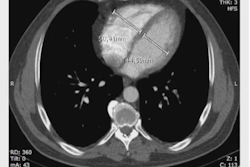

A 73-year-old woman with a suspicious lung nodule was referred to our division for F-18 FDG PET/CT exam. She was vaccinated four days before PET/CT. The lung nodule did not show any pathological FDG uptake; however, high tracer activity was detected on her right arm, where she was injected, and multiple hypermetabolic lymph nodes in the right axilla (arrows). Moreover, PET/CT showed high tracer activity in the liver (black arrows), spleen (triangular arrows), and bone marrow (small triangular arrows) as the result of systemic immune response after vaccination. The tracer defect in the liver was due to the known cyst. (A) fusion scan, (B) PET, (C) maximum intensity projection. Image courtesy of Scientific Reports.